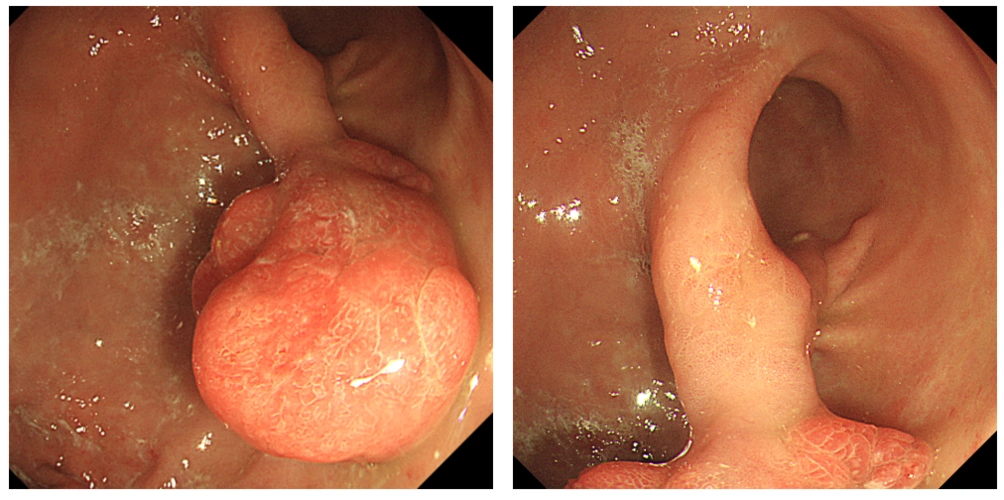

这样的胃息肉你见过吗